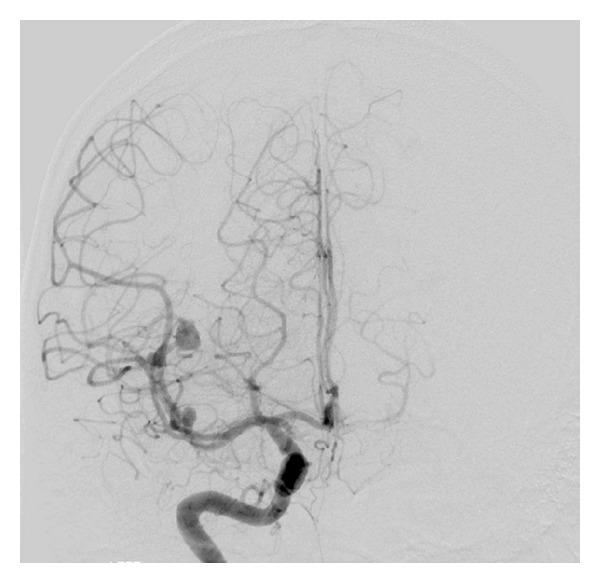

Introduction. Intracranial aneurysms associated with Behçet's disease (BD) are a rare occurrence. They are fragile, thin-walled pseudoaneurysms, which have high tendency to rupture and present a therapeutic challenge. Case Presentation. We report a 26-year-old male with BD presented with subarachnoid hemorrhage due to ruptured middle cerebral artery aneurysm. Additionally, two unruptured aneurysms were identified. He underwent endovascular embolization using Onyx with successful obliteration of the ruptured aneurysm. Medical therapy resulted in regression of one and resolution of the other aneurysms. Conclusion. We describe the first report of the application of Onyx for obliteration of ruptured cerebral aneurysm in BD as a feasible and safe therapeutic option for patients who are not candidates for other techniques.

引言。与白塞病(BD)相关的颅内动脉瘤较为罕见。它们是脆弱的薄壁假性动脉瘤,极易破裂,给治疗带来挑战。病例报告。我们报告一例26岁患有白塞病的男性,因大脑中动脉动脉瘤破裂出现蛛网膜下腔出血。此外,还发现了两个未破裂的动脉瘤。他接受了使用Onyx的血管内栓塞治疗,破裂的动脉瘤成功闭塞。药物治疗使其中一个动脉瘤缩小,另一个动脉瘤消失。结论。我们描述了首例将Onyx应用于闭塞白塞病破裂脑动脉瘤的报告,对于不适合其他技术的患者而言,这是一种可行且安全的治疗选择。